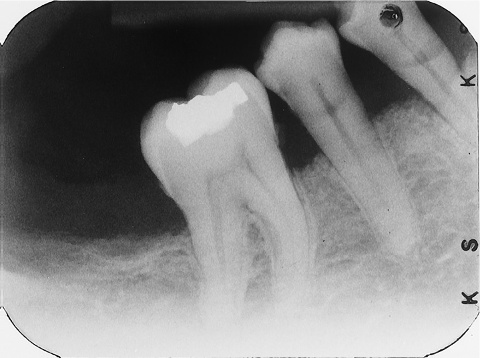

3. (Select ONE OR MORE correct answers)

The radiograph shows evidence of